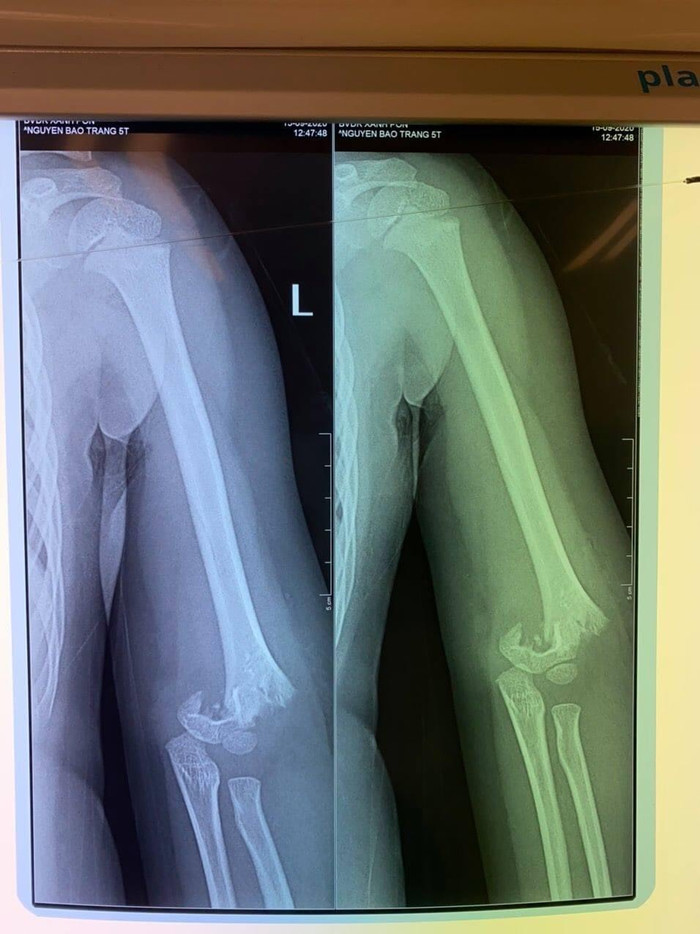

Hình ảnh xương khuỷu tay bé gái bị gãy lìa.

Tại bệnh viện, khi cô giáo thông báo cho mẹ cháu bé vào làm thủ tục để nhập viện, chị H. vô cùng bất ngờ khi biết con bị mổ cấp cứu, có nguy cơ bị liệt, đau đớn hơn khi xem phim chụp thấy hình ảnh xương ở khuỷu tay của con đã bị gãy lìa.